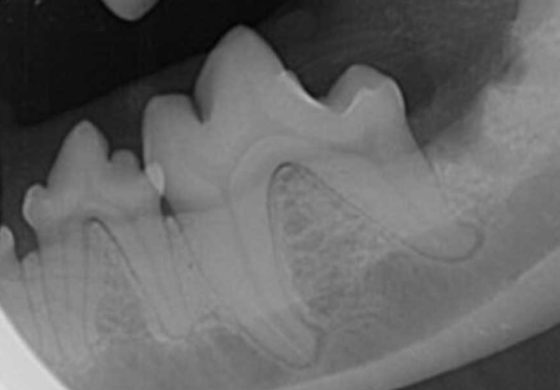

Figure 3. Dental radiograph of left mandibular first and second molar teeth in a mature dog with severe periodontal disease. Horizontal bone loss (overall loss of alveolar bone height) is present, as is vertical bone loss involving the mesial root of the first molar tooth and both roots of the second molar tooth. This explains the probing examination findings of increased probing depths in these regions, a stage three furcation exposure of the second molar tooth and a stage two furcation exposure of the first molar tooth. A periapical lesion of the distal root of the first molar tooth, which represents a perio-endo lesion, is an additional radiographic finding.